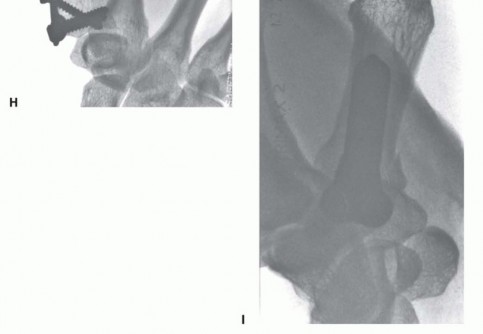

Open Reduction and Internal Fixation (ORIF) - Wagner Approach

For fractures with large volar-ulnar fragments (>20% of the articular surface), displaced Rolando fractures, or cases where closed reduction fails, ORIF is unequivocally mandated. The classic Wagner approach provides unparalleled exposure to the thumb CMC joint. A curvilinear incision is made along the glabrous border of the thenar eminence, curving dorsally at the level of the CMC joint.

Image

Meticulous superficial dissection is required to identify and protect the sensory branches of the superficial radial nerve dorsally and the palmar cutaneous branch of the median nerve volarly. The thenar musculature (abductor pollicis brevis and opponens pollicis) is sharply elevated from the metacarpal shaft and retracted volarly. The joint capsule is then incised longitudinally or in an L-shaped fashion to expose the articular surface. The hematoma is evacuated, and the fracture fragments are meticulously debrided of interposed soft tissue.

For a large fragment Bennett fracture, the shaft is reduced to the volar-ulnar fragment using a pointed reduction clamp. Provisional fixation is achieved with a K-wire. A 1.5mm or 2.0mm lag screw is then placed perpendicular to the fracture plane. The near cortex must be overdrilled (gliding hole) and the far cortex underdrilled (thread hole) to achieve true interfragmentary compression. The screw head should be countersunk to prevent hardware prominence beneath the thenar muscles.